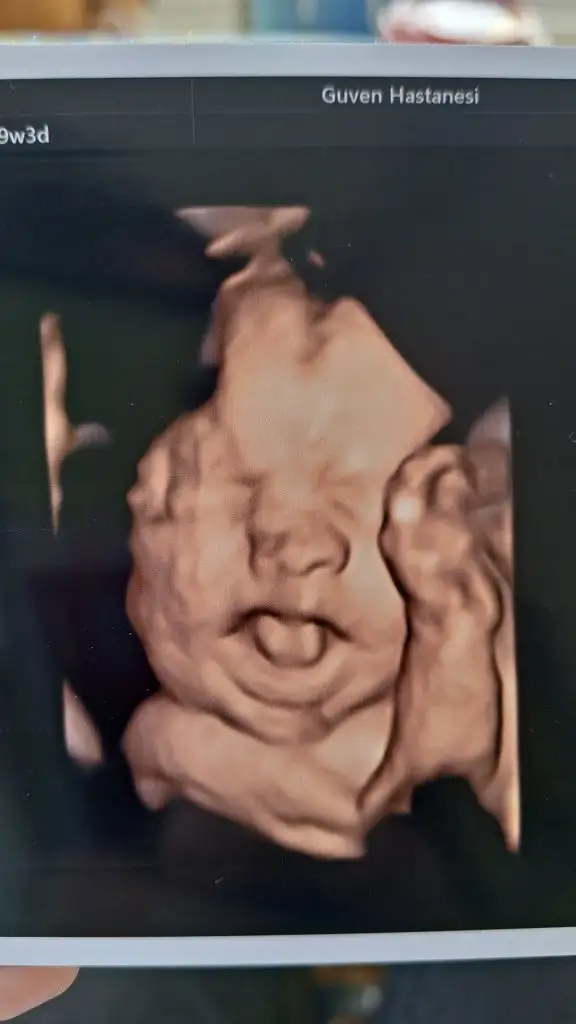

anamm doğuştan estetikli maşallah